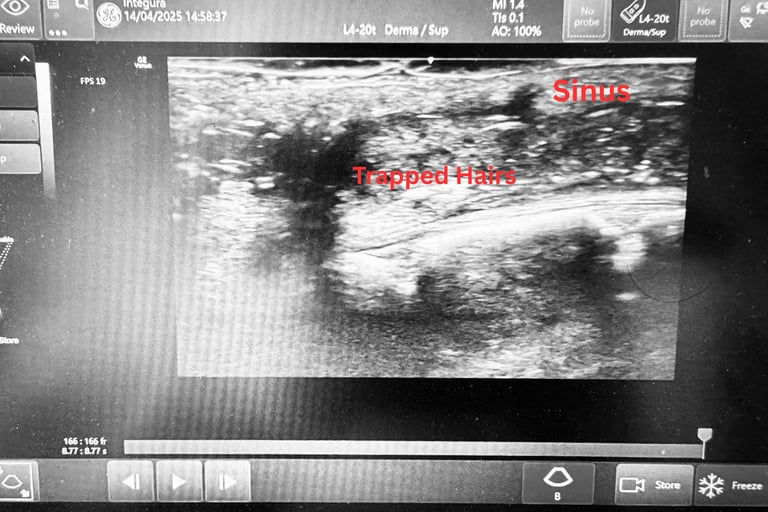

A major differentiator of our practice is the routine use of ultrasound imaging before, during and after treatment. Before treatment, ultrasound helps map the sinus tracts accurately, identify hidden branches, and detect retained hairs within scar tissue from previous inflammation. During minimally invasive procedures, ultrasound guidance and the use of a guidewire under ultrasound vision help ensure accurate access without creating false passages or new tracts.

Following treatment, ultrasound assessment enables us to monitor healing in a controlled, predictable manner, rather than relying solely on patient-reported symptoms. This reduces uncertainty and supports more effective long-term management.